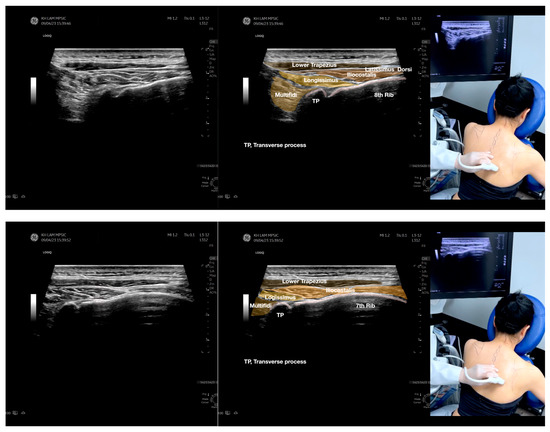

Figure 4.

Sonoanatomy of the medial edge of the scapula, its related muscles, and the infraspinatus fascia. The step-by-step scanning techniques of these structures illustrated in this figure have been shown in Video S8. Available online: https://www.dropbox.com/s/iaej3rxhl83kqt4/Figure%204.docx?dl=0 (accessed on 1 January 2023).